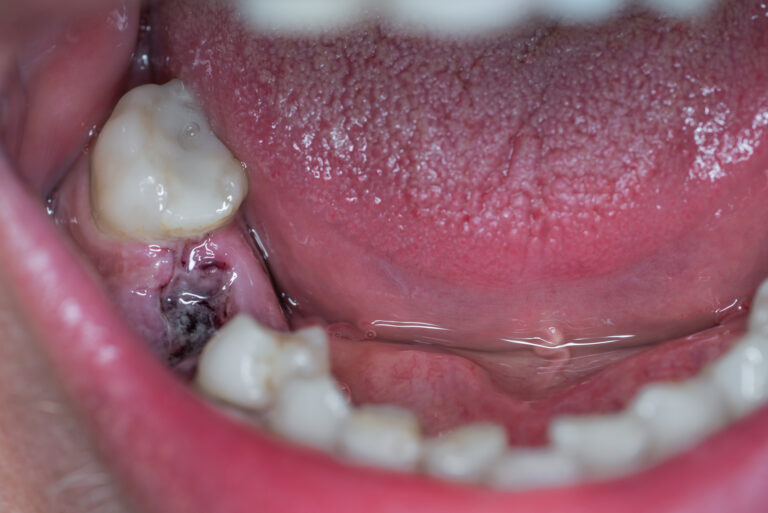

Pics of my dry socket! r/wisdomteeth Dry Socket Wisdom Teeth Smoking  Dry socket is one of the postoperative complications of. Poor oral hygiene can place you at greater risk of dry socket.   dry socket, clinically called alveolar osteitis, is a healing complication that occurs after tooth extraction, often with wisdom teeth removal.   you can help promote healing and reduce symptoms during treatment of dry socket by following instructions for.. Dry Socket Wisdom Teeth Smoking.